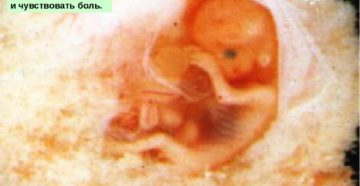

12 неделя беременности 12 неделя беременности по, так называемому, акушерскому календарю, которым привыкли руководствоваться медики,…

Как развивается плод на 10 недели беременности › Зачатие › Ожидание чуда меняет женщину, открывая…